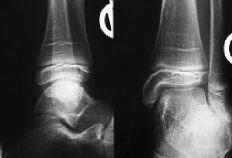

ABFigura 1. A: Localización de las lesiones osteocondrales astragalinas en la clínica ortopédica de Würzburg. B: Lesión osteocondral en la carilla lateral del astrágalo de origen traumático directo.

En los 64 pacientes se pudo realizar el diagnóstico en 63 casos mediante radiografías del tobillo, predominando las zonas claras (56%) y observando cuerpos libres en sólo tres ocasiones (5%) (Fig. 2). En la radiología postoperatoria se observaron dos datos interesantes; el primero es que en 18 casos (28%) había ausencia de lesión osteocondral en la fase de seguimiento, mientras en los demás existía bien una zona clara (19 casos) o irregularidades en el contorno articular con depresiones o impresiones de ésta (24 casos) (Fig. 3). En 16 casos se realizó una RM y en cuatro se realizó una TAC. El objeto de estas exploraciones fue el obtener más información sobre el estado de la lesión, con excepción del mencionado caso en el que radiográficamente no se pudo ver la existencia de dicha lesión y cuyo diagnóstico se hizo a través de la RM.

ABCFigura 7. Paciente de 11 años de edad. A: Rx preoperatorias. B: RM. Radiológicamente se consideró un Grado 3 a 4 de lesión. Intraoperatoriamente se encontró un reblandecimiento del cartílago, demarcado y sin fisuras. Se hizo una perforación retrógrada bajo control radiográfico y artroscópico. C: Resultado final tras 3 años de seguimiento; la paciente está asintomática.